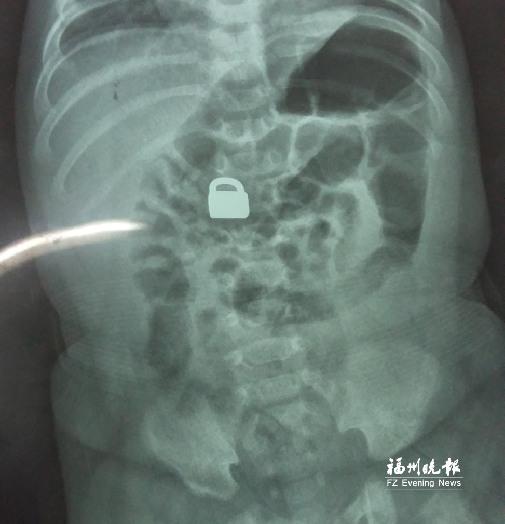

7.25龙岩当地医院拍的X光片显示,平安锁在宝宝体内

“X光片显示,那是一把1.5厘米×0.9厘米的平安锁,有指甲盖大小,已经到了宝宝的小肠处。”7月28日,陈惠萍见到宝宝时,吃了一惊,“他真的好小,被抱在妈妈怀里,眼睛微微睁开,我估计他的世界还是混沌的,没想到就已经接受了这么大的挑战。”